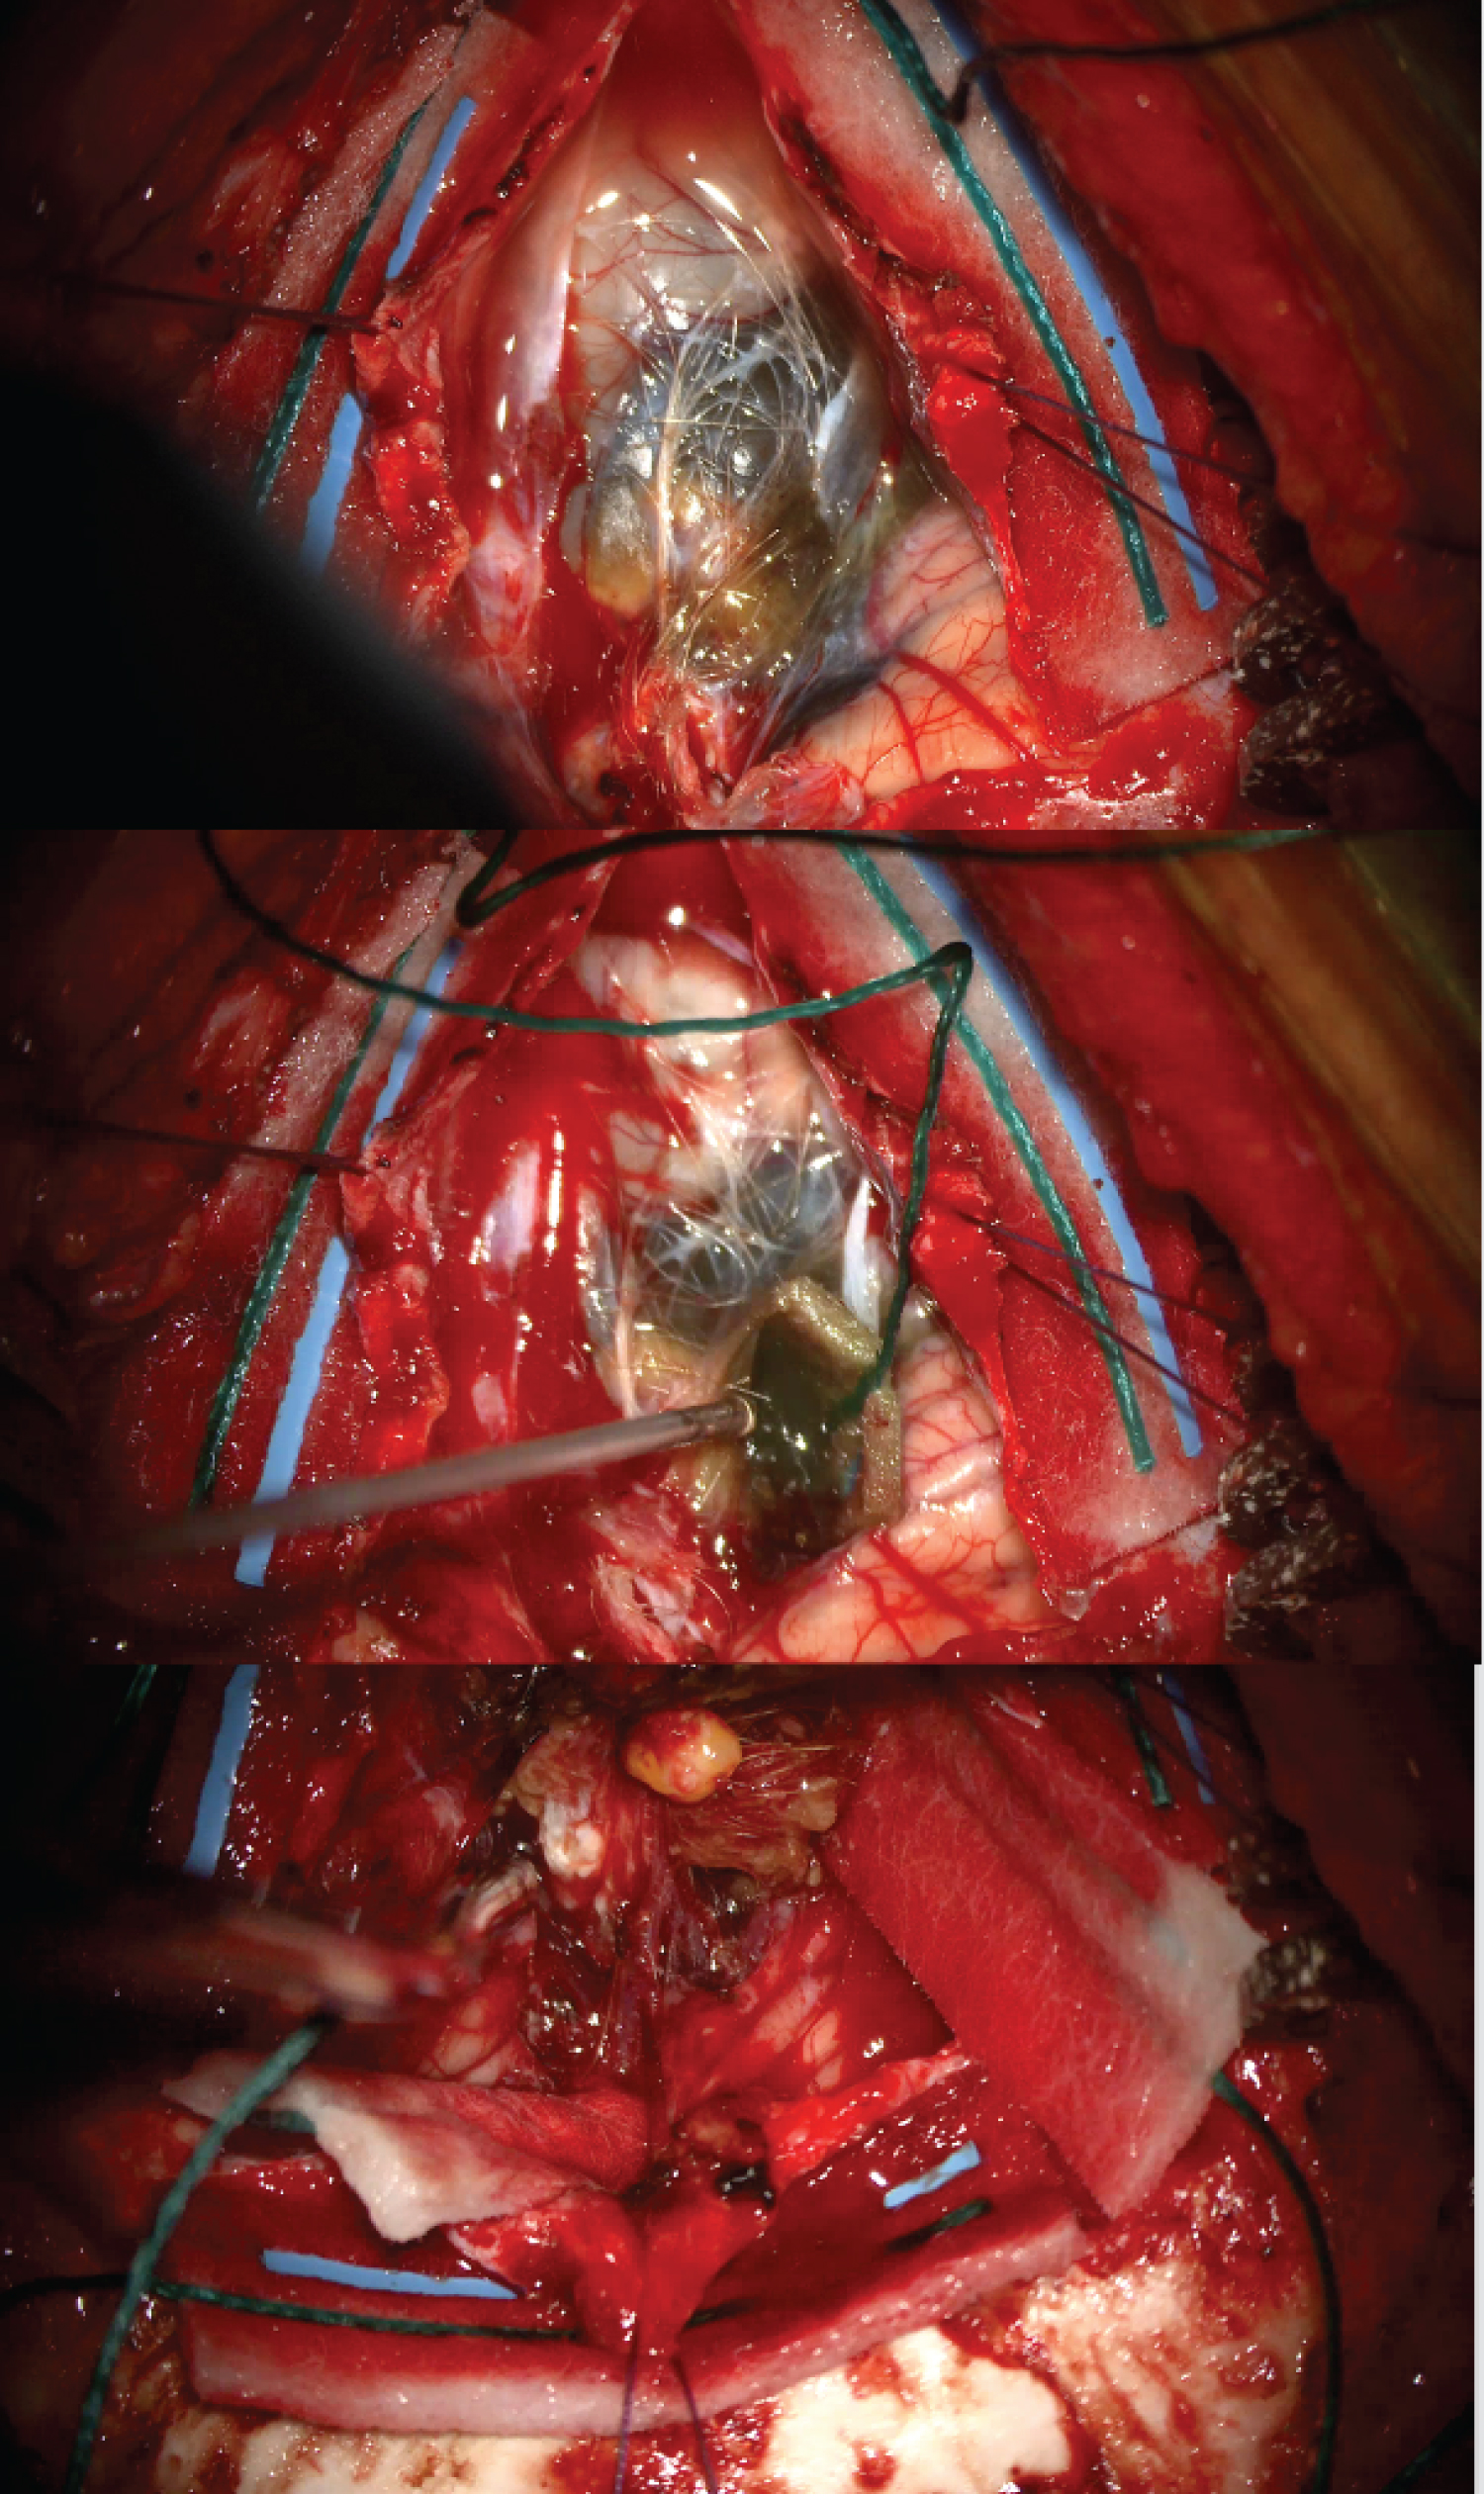

A posterior fossa craniotomy was performed. During a midline hair shave, a small dermal sinus containing hair was noted. Afterdural opening, non-pigmented hair was visible over a lobulated green-brown mass within the cerebellum (Figure 3). The mass consisted of cysts containing viscous green fluid and a calcified tooth-like lesion.

Figure 3: Intra-operative photographs taken in prone position during posterior fossa craniotomy. Orientation: Top of photograph = inferior cerebellum (A) Non-pigmented strands of hair visible over posterior fossa mass following dural opening; (B) Green coloured viscous cyst contents; (C) Calcified tooth-like mass within lesion. View Figure 3